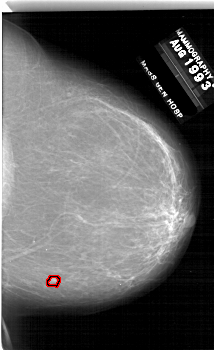

A_1857_1.LEFT_CC

RIGHT_CC LINES 6646 PIXELS_PER_LINE 4051 BITS_PER_PIXEL 12 RESOLUTION 43.5 OVERLAY

FILE: A_1857_1.RIGHT_CC.OVERLAY

TOTAL_ABNORMALITIES 1

ABNORMALITY 1

LESION_TYPE MASS SHAPE IRREGULAR MARGINS ILL_DEFINED

ASSESSMENT 4

SUBTLETY 3

PATHOLOGY BENIGN

TOTAL_OUTLINES 1

BOUNDARY